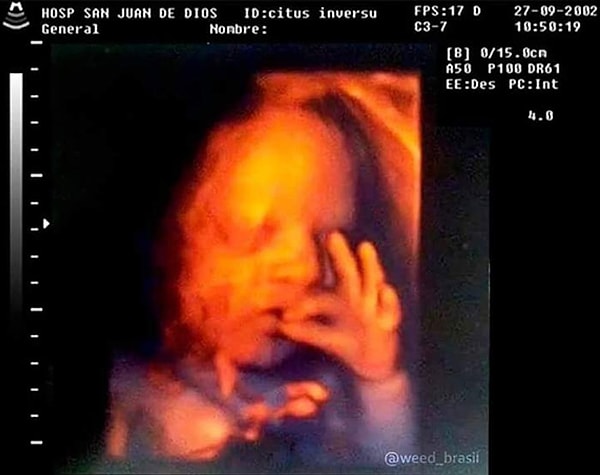

В Facebook есть замечательная страница 'Kids in Predicaments' (Дети в затруднениях), на которой собраны фотографии всех забавных и нелепых ситуаций, в которые попадают наши маленькие исследователи.